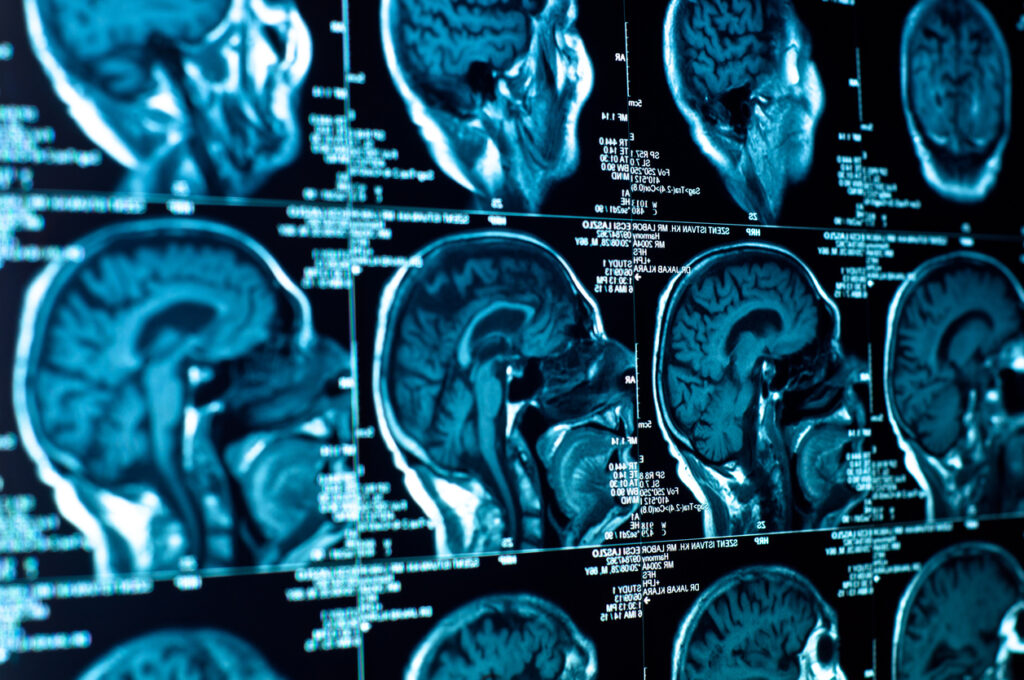

This research uses a type of radiotherapy, Gamma Knife, for glioblastoma. This is not usually used for this high grade tumour. Gamma Knife surgery is a computer-guided treatment that delivers highly focused radiation to tumours, and is done so painlessly.

The study shows that Gamma Knife is a feasible treatment for local control and survival outcomes. It concluded that a boost of Gamma Knife can increase progression free and overall survival in people with a GBM.